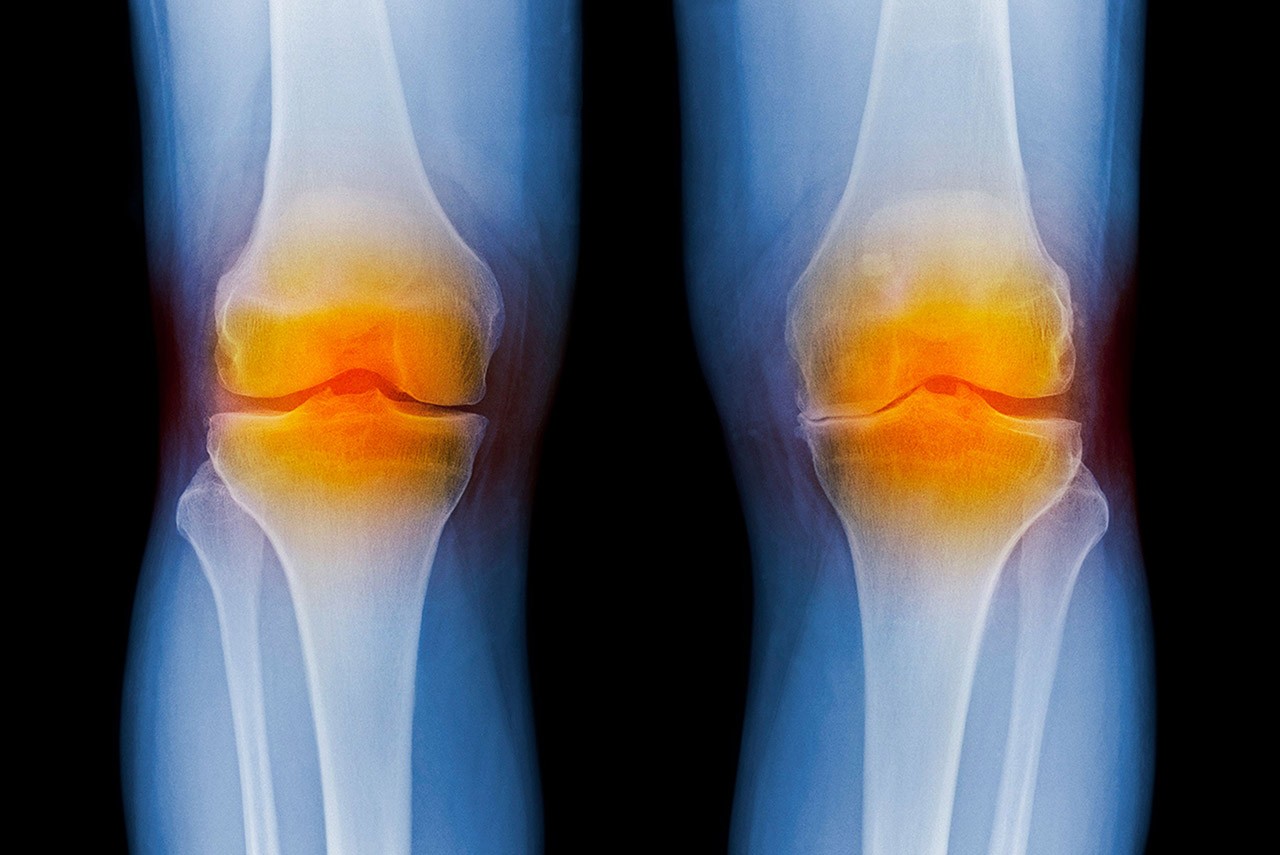

Dean Marcolongo and the team developed biomimetic proteoglycans, or BPGs—lab-engineered molecules that can withstand the inflammatory enzyme attacks that typically cause joints to break down. When these BPGs are injected into joints, the researchers found they can molecularly engineer damaged cartilage, repairing degenerated tissues.

It’s a new strategy for patients with osteoarthritis, a degenerative disease of the joints for which there is no cure. Today, if a patient has early arthritis symptoms in their joints, they have limited options—take ibuprofen, get a steroid injection, undergo physical therapy or wait until later in life to get a total replacement.

“We don’t have many treatments to treat early arthritis and stop the progression to painful and debilitating symptoms,” says Dean Marcolongo. The treatment she helped develop has potential to fill that gap. It’s minimally invasive, requiring just a simple knee injection.